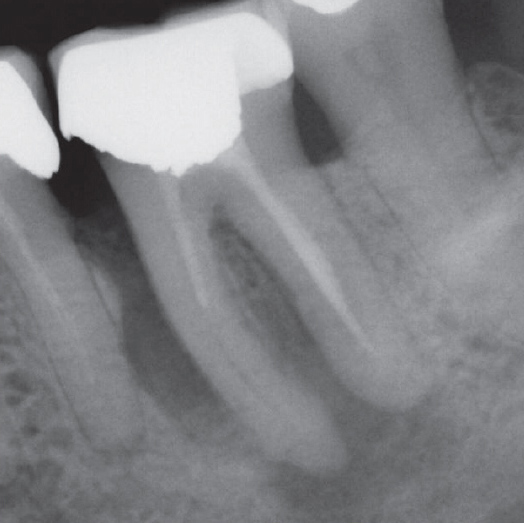

Before

Before Root Canal treatment